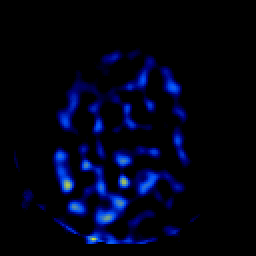

SPECT TL Study #6 -- Slice #46

[Home][Help][Clinical][Tour 1][Tour 2][Tour 3] Slice 46